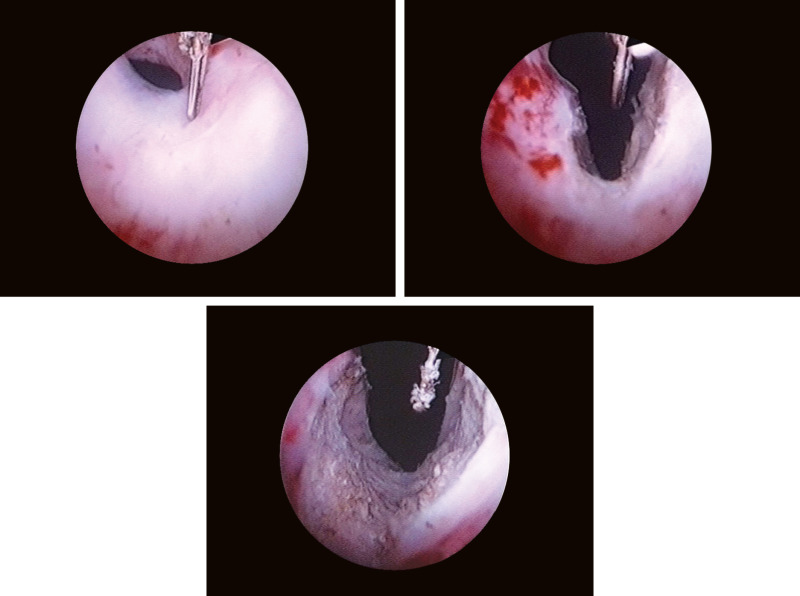

Κατά την επέμβαση δεν αφαιρείται προστατικός ιστός, αλλά γίνεται διάνοιξη της ουρήθρας στο σημείο που ενώνεται η ουροδόχος κύστη με την ουρήθρα ( αυχένας) με την πραγματοποίηση βαθιών διατομών. Οι διατομές αυτές διανοίγουν την προστατική μοίρα της ουρήθρας και έτσι βοηθούν να γίνει η ούρηση ευκολότερη.